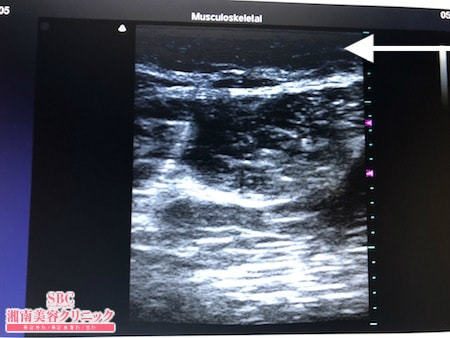

No.246239【脂肪吸引】? 【動画あり】湘南美容外科全ドクターの脂肪吸引最高責任者である竹田先生による脂肪吸引のフォトギャラリー!もともとセルライトが気になっていたので脂肪吸引で解消する!術中3Dタッチビュー・左太もも後面

その術中変化を紹介しましょう。